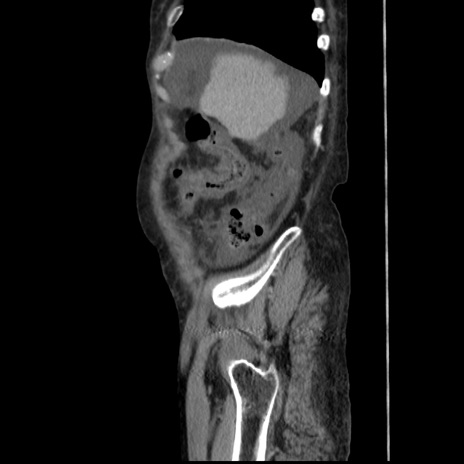

症例31(矢状断像)

【症例】80歳代 女性

【主訴】腹部膨満感

【現病歴】他院にて肝硬変にてフォロー中。1週間前から便秘、腹部膨満感、臍部腫瘤あり受診となる。

【既往歴】肝硬変

【身体所見】腹部膨隆あり、皮膚変化なし、疼痛なし。

【データ】WBC 4600、CRP 0.25